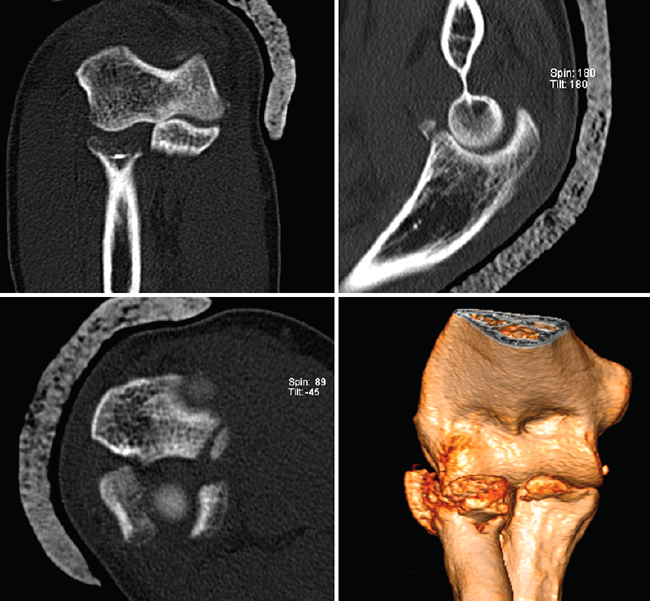

Figura 14. Tríada terrible de codo derecho donde puede apreciarse en las imágenes de tomografía computarizada la fractura de la cabeza del radio, la fractura de la coronoides y la subluxación posterolateral de la ulnohumeral.

El mecanismo lesional de estas lesiones es el patrón de inestabilidad posterolateral descrito por Morrey y O’Driscoll(15).